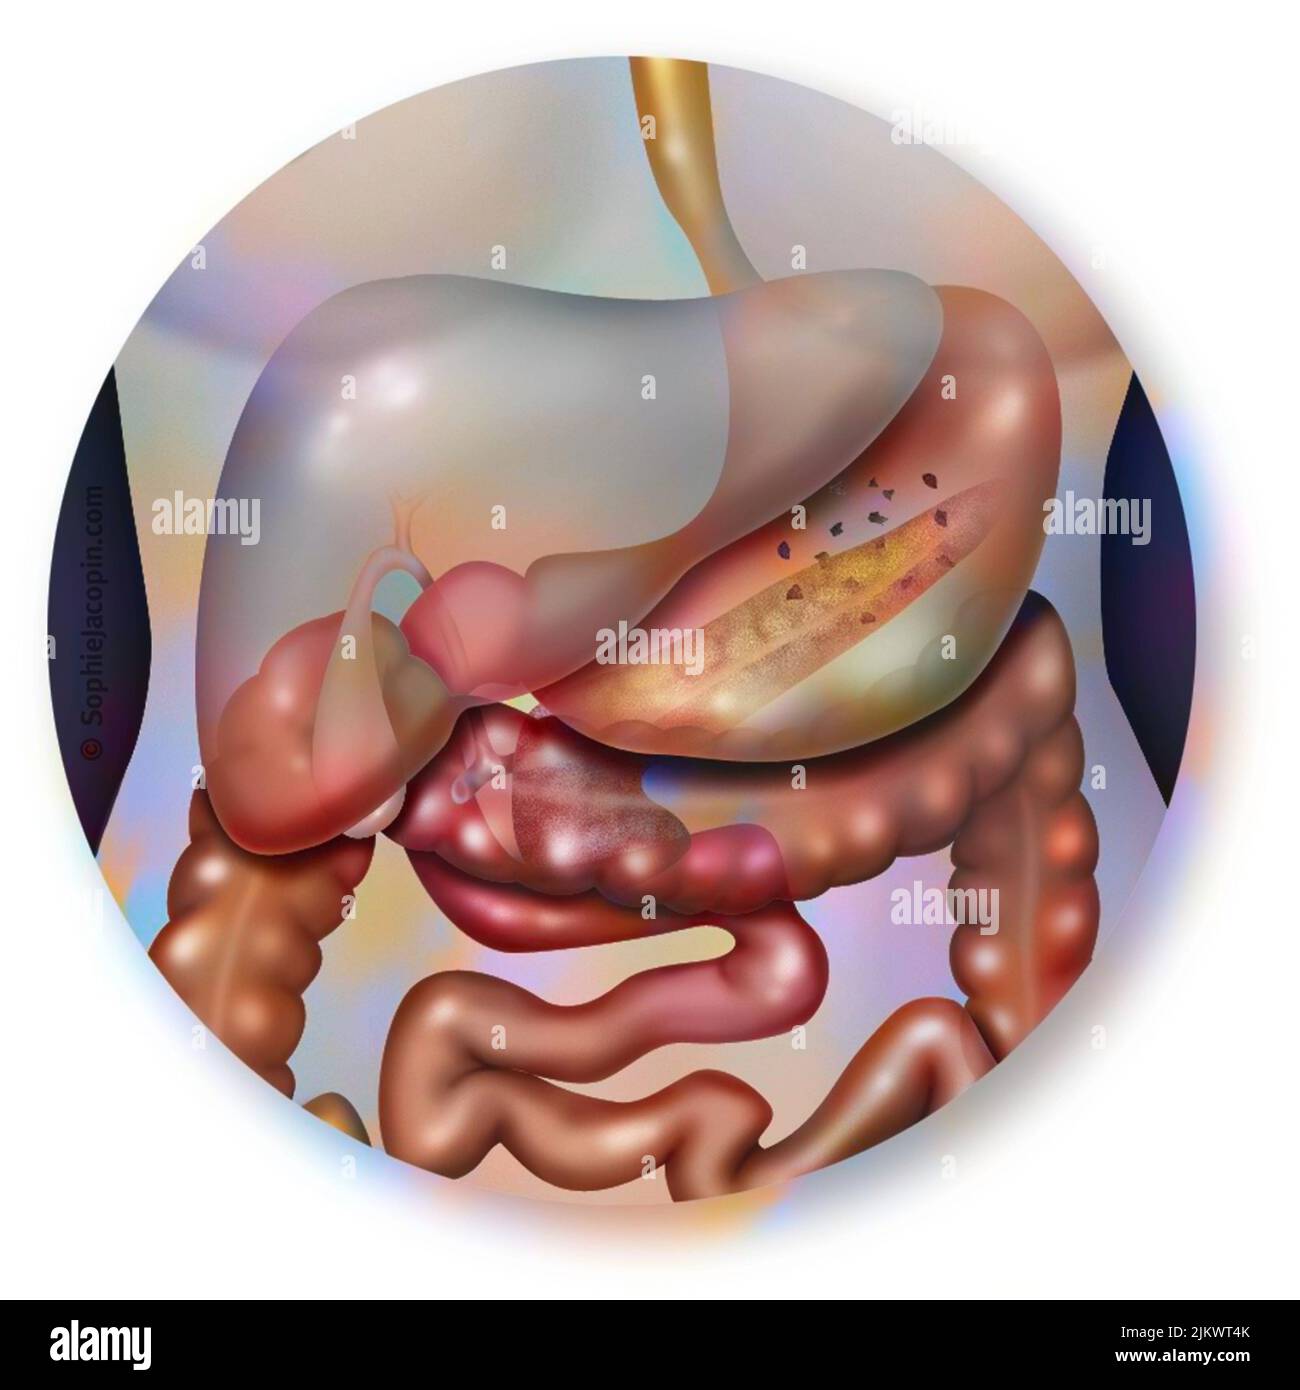

(4,132)Page 1 sur 42

Résultats de la recherche pour les photos et les images (4,132)

Page 1 sur 42